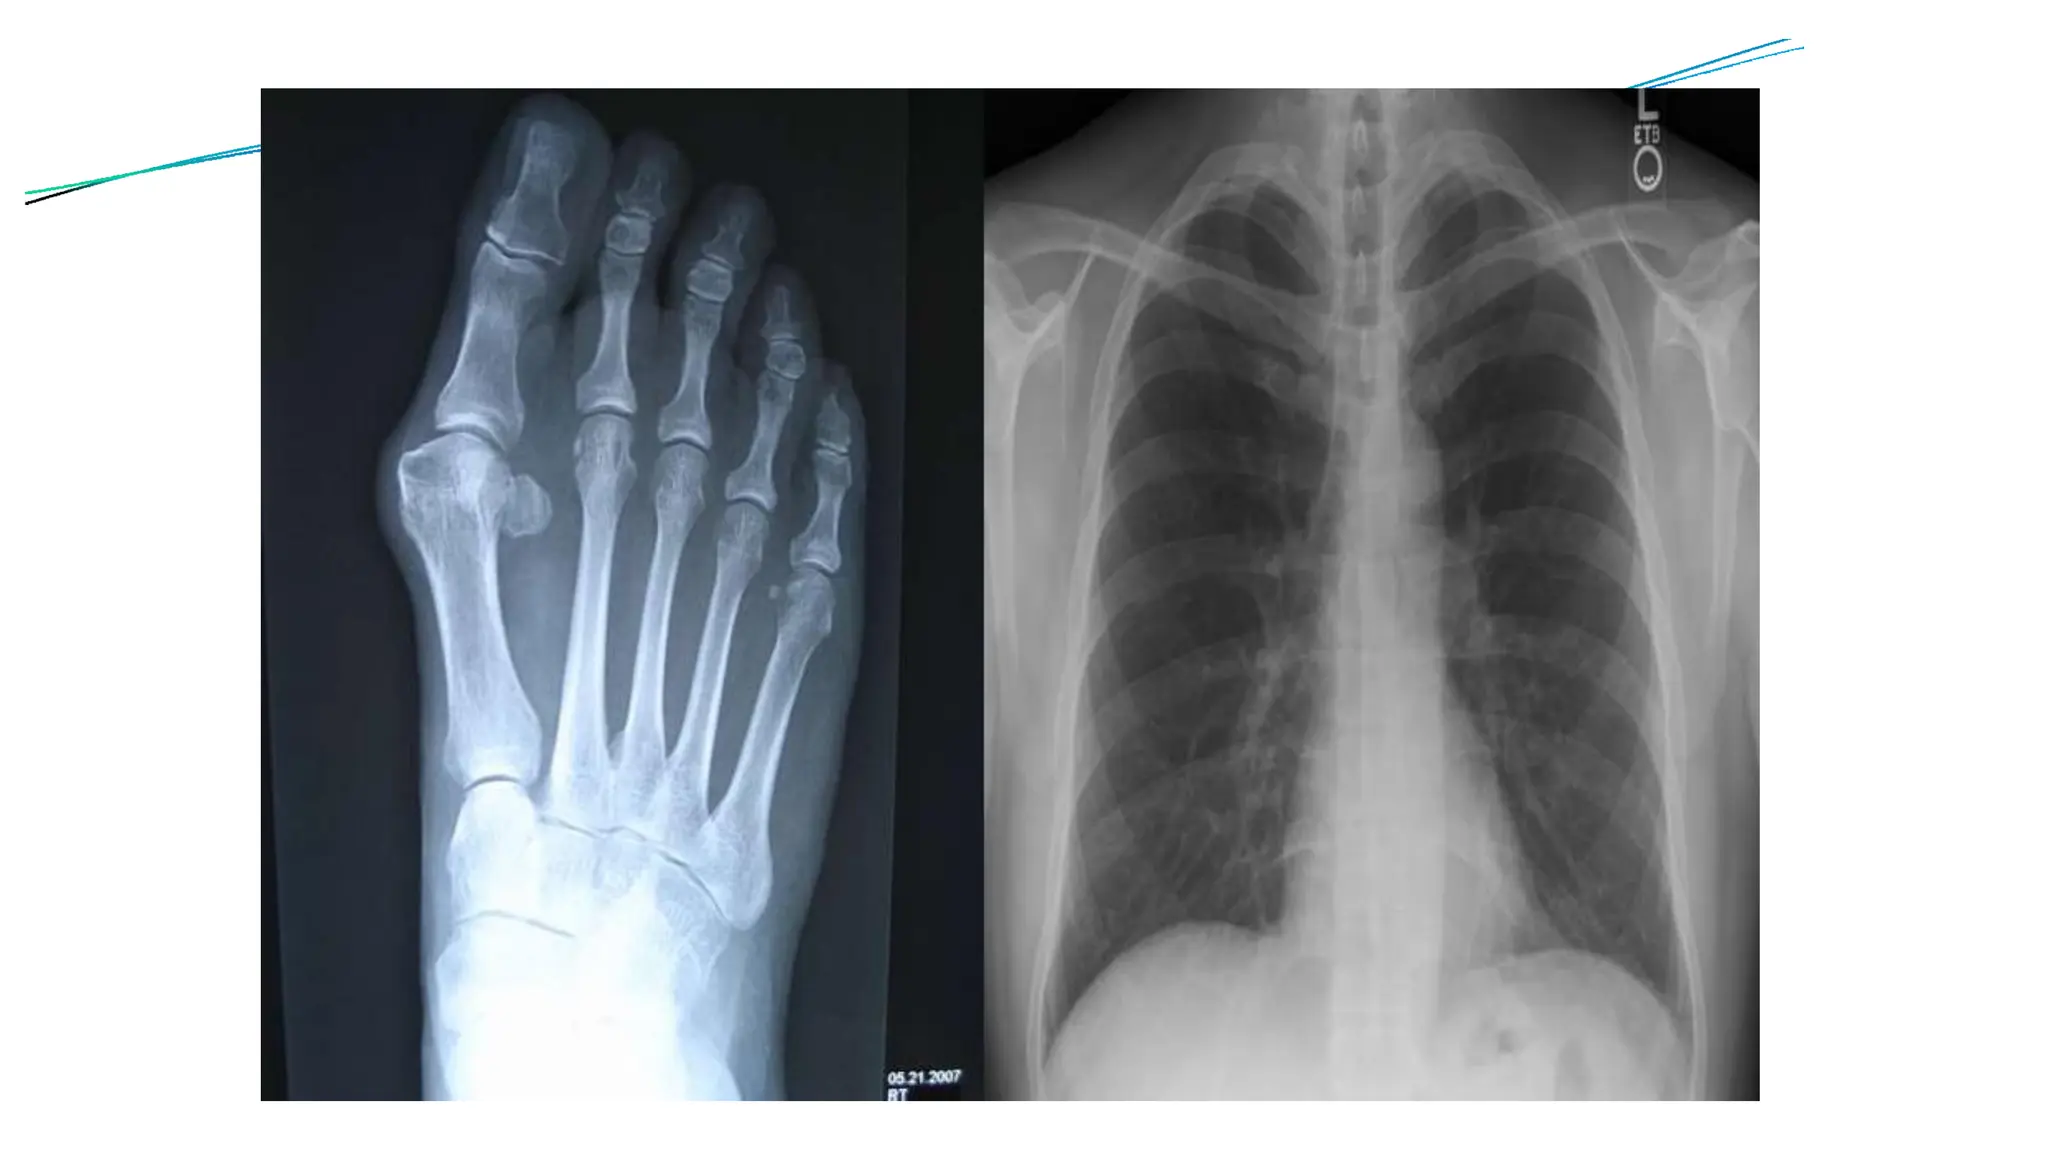

⚫X-rays are basically electromagnetic radiations which are used to

⚫The images show the parts of your body in different shades of

⚫Calcium in bones absorbs x-rays the most, so bones look white.

Fatand othersoft tissues absorb less, and look gray.

⚫Airabsorbs the least, so lungs look black.

❖X-rays are particularly effective in diagnosing

▪ fracture detection: used to check for broken bones or

fracture

✓ It provide clear image of bone structures, allowing

doctors to see the location, type and the severity of

the break

▪Joint problems: Detecting Arthritis and joint dislocation

▪Lung condition: Diagnosing pneumonia, tuberculosis,

lung cancer and other pulmonary diseases